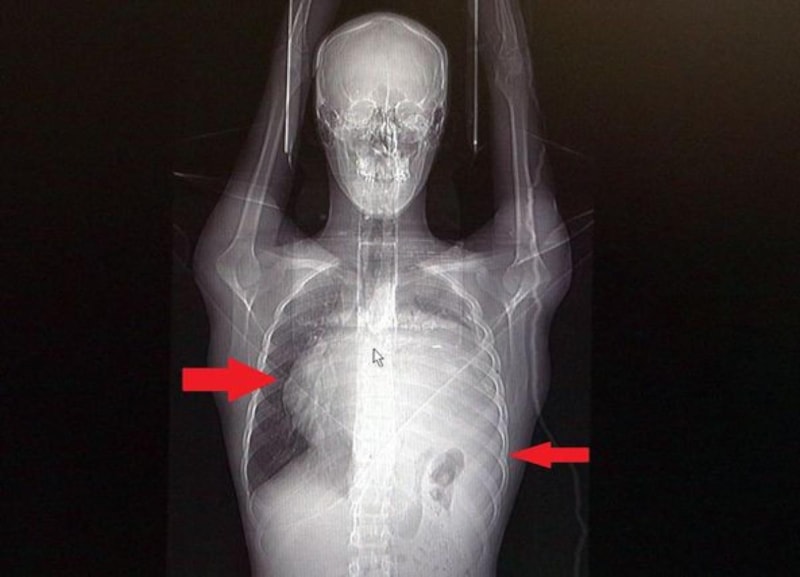

21 yaşındaki genç adamın kalbini 12 cm sağa kaydıran 6.5 kiloluk dev tümörden ameliyatla kurtuldu. Doktorlar, tümörün baskı yaparak sol akciğeri kağıt gibi ezdiğini söyledi.

Sol akciğerinin yüzde seksenini kağıt gibi ezen, kalbini göğüs duvarında 12 santim sağa kaydıran ve hem kalbe hem beyne giden ana damarlara baskı yapan 6.5 kilo ağırlığındaki dev tümör, doktorların birlikte girdiği operasyonla başarılı şekilde çıkarıldı.

Göğüs boşluğunda kemik kafesi içinde olduğu için, itebileceği iki organ var; biri kalp, diğeri de akciğerler. Soldan sağa doğru büyüdüğü için kalbi tamamen göğüs boşluğunun sağ tarafına itmiş ve kalbe giren ve kalpten çıkan bütün büyük damarları da yer değiştirmenin etkisiyle bükülmüş durumdaydı. Bu nedenle vücuduna yeterince kan gitmiyordu. Ağustos ayının başında portakal büyüklüğündeyken kitle Eylül sonuna irice bir kavun, Ekim ayına geldiğimizde ise bir karpuz büyüklüğüne ulaştığı için, kitlenin büyüme hızı bizi acilen ameliyat yapmaya yöneltti. Yaklaşık 8-10 kat hacimsel olarak artmıştı. Sol akciğer tamamen ezilmiş ve kağıt haldeydi, alt lobu anestezi ekibimiz yüksek basınç uygulayarak tekrar şişirdi. Çok fazla vaktimiz yoktu, kitle basısından dolayı yaşamla bağdaşmayacağından dolayı hızlı hareket etmek zorundaydık. Bize geldikten üç gün sonra hemen ameliyata aldık çünkü tümörden ziyade onun yaptığı baskıdan kaynaklı hayati riski vardı.